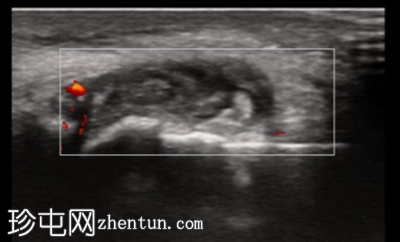

纵轴切面

第一跖趾关节纵轴切面

关节积液伴轻度滑膜增生。高回声不规则沉积物,符合尿酸钠晶体沉积的典型表现。彩色多普勒成像显示滑膜充血活跃,符合急性炎症活动。